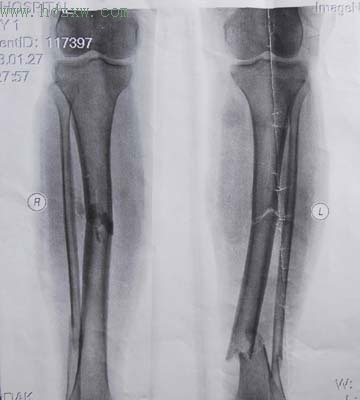

大概我們奶奶身體太好了,所以一些老年人會有的疾患和小毛病我們也沒注意。奶奶不管天晴或小雨都到附近”仙蹟岩”走走,這已是慣例了,誰也沒想到奶奶有「骨質疏鬆症」。出事的那天就是小雨天,仙蹟岩太多的梯子要爬,就是一個膝關節用力,奶奶的骨頭壓碎了,關節腫的好大。

但是我們大家知道這事時,奶奶自己回了家,實在痛到沒辦法,才打電話給大姑,送著奶奶去醫院,也打了好久的石膏。後來雖說可以活動,卻演變成老人的”關節炎”,5-.6年後奶奶總有點因關節疼而跛腳。我曾經問婆婆:「為什麼你一個人走下山?」我家奶奶回答,她不好意思麻煩人家扶她下山。當然,我猜測出事的地方,離山下可能不會很遠,要不然這麼痛,她可以求救卻沒有求救。